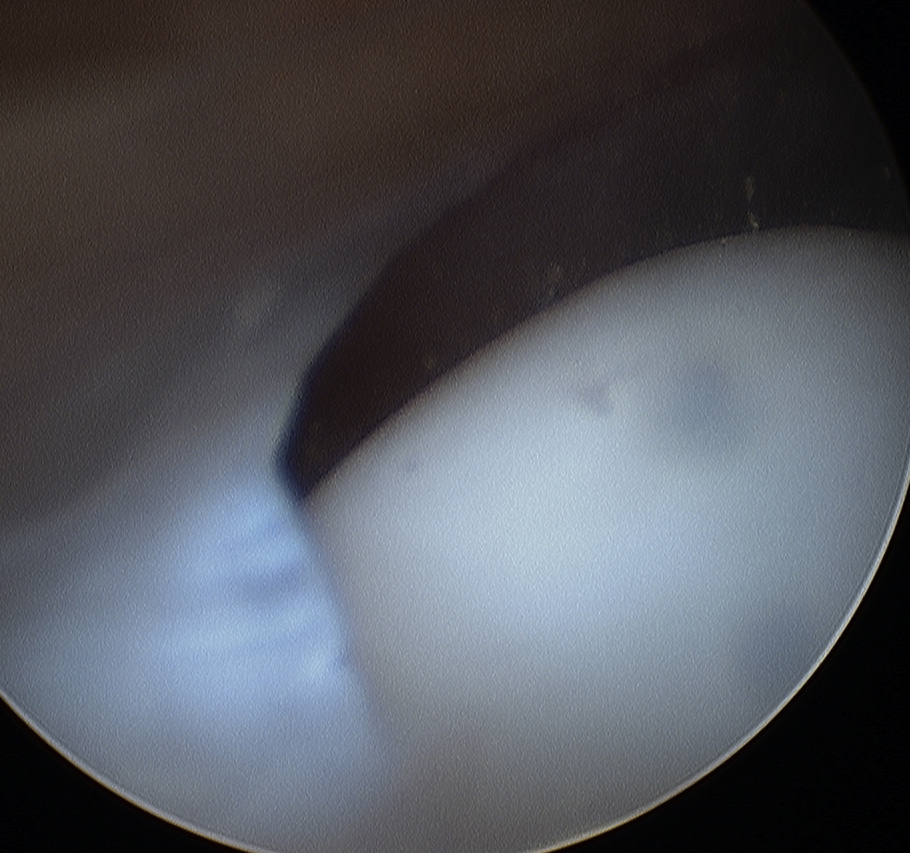

Arthroscopy

Normal

- thin

- no evidence inflammation

- no evidence chondral damage